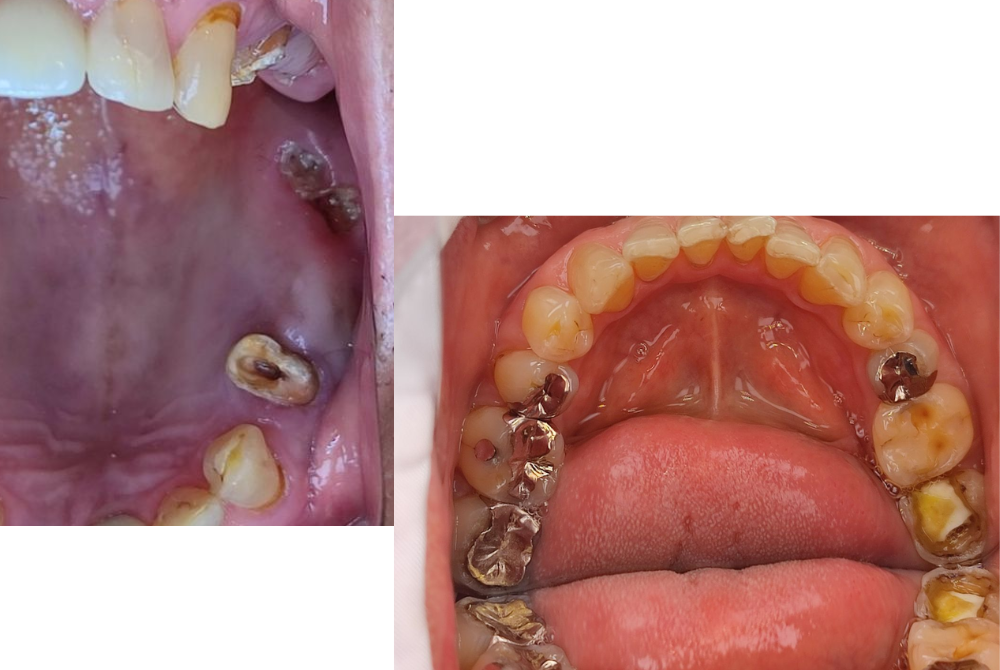

C3(神経に到達した虫歯)

ズキズキした痛み、夜間の激痛などが特徴。

ここまで来ると神経が炎症を起こしているため、根の中を掃除する「根管治療」が必要になるケースが多くなります。

C4(歯の根まで進行した虫歯)

歯がほとんど崩れ、根しか残っていない状態です。痛みが引く場合もありますが、それは神経が死んでしまった証拠。 抜歯が避けられないこともあり、早期発見が何より大切です。